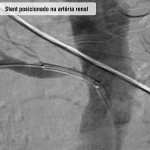

Angioplasita renal

O que é

Técnica cirúrgica minimamente invasiva indicada, basicamente, para casos de estenoses críticas (acima de 70%) de uma ou de ambas as artérias renais com comprometimento da função dos rins.

Como funciona

Todo o procedimento é realizado “por dentro dos vasos sanguíneos”, através de uma punção na região da virilha. Não há cortes ou necessidade de pontos. Uma anestesia local é empregada junto com uma sedação leve.

São introduzidos cateteres até o vaso acometido através do qual é implantado um stent (tubo metálico que mantém o vaso aberto), que é expandido por um balão. A taxa de sucesso do procedimento é de 95%, ou seja, em apenas 5% das vezes não é possível implantar o stent.

Fotos